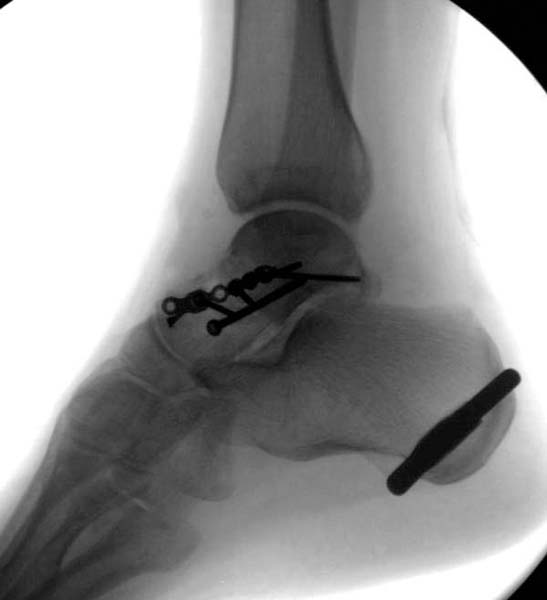

Трудно выбрать приоритет, когда имеется одинаковые по значимости, по сложности повреждения и с вовлечением различной локализации. У пожилых переломо-вывих головки бедра можно было бы проигнорировать, но у молодых такое решение привело бы к катастрофе, и поэтому приоритет первичной фиксации отдали решению переломо-вывиха таранной кости и головки бедра.

Больная стабильная после хирургических мероприятии и получив добро, приступили к закрытому вправлению таранной кости с укладкой наружного фиксатора. Затем укладка больную на бок и открытый остеосинтез перелома-вывиха головки бедра.

После спадения отека на стопе произведена фиксация тарана. Кстати, коллеги пересмотрели первоначальную консультацию по позвоночнику и на двух уровнях провели фиксацию. Из-за длительного постельного режима без нагрузки таз не стали оперировать...